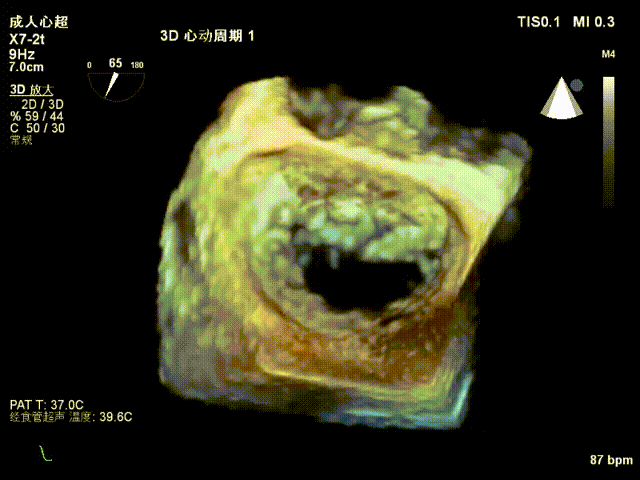

术前超声评估

前瓣长度:28mm;后瓣长度:15mm;前、后瓣叶对合深度:11mm;对合高度2mm;瓣叶及瓣环无钙化,二尖瓣有效开口面积 4.0m²。诊断重度功能性二尖瓣反流FMR。

术前TEE显示重度功能性二尖瓣反流,反流位于A2/P2;